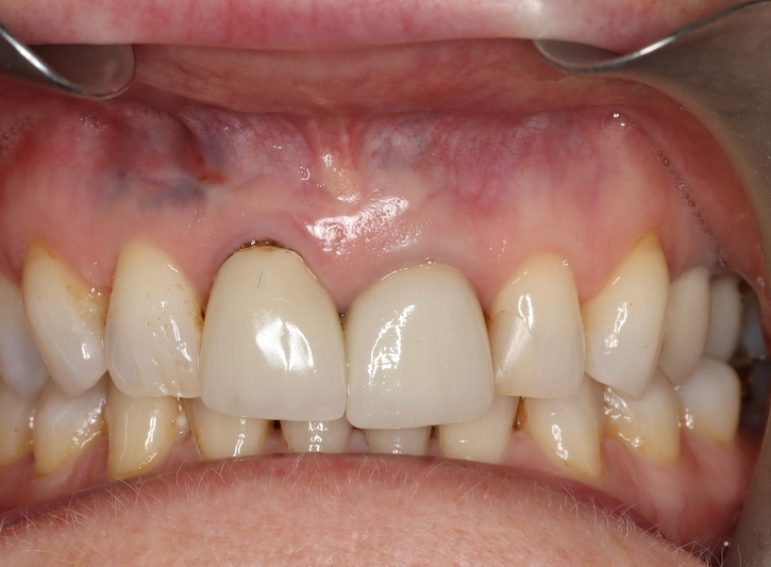

Case 26 – Endodontics

Repeat apicectomy with grafting